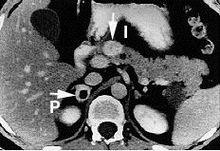

An image of a patient with pheochromocytoma. In patients with this disease, a catecholamine secreting tumor is formed, and causes excess CNS stimulation, such as excess sweating and tachycardia. Nonselective alpha blockers, such as phenoxybenzamine or phentolamine, can be used to mitigate this disease.

Pheochromocytoma is a disease in which a catecholamine secreting tumor develops.[2][20] Specifically, norepinephrine and epinephrine are secreted by these tumors, either continuously or intermittently.[21] The excess release of these catecholamines increases central nervous system stimulation, thus causing blood vessels to increase in vascular resistance, and ultimately giving rise to hypertension.[20] In addition, patients with these rare tumors are often subject to headaches, heart palpitations, and increased sweating.[2]

Phenoxybenzamine, a nonselective α1 and α2 blocker, has been used to treat pheochromocytoma.[21] This drug blocks the activity of epinephrine and norepinephrine by antagonizing the alpha receptors, thus decreasing vascular resistance, increasing vasodilation, and decreasing blood pressure overall.[21]